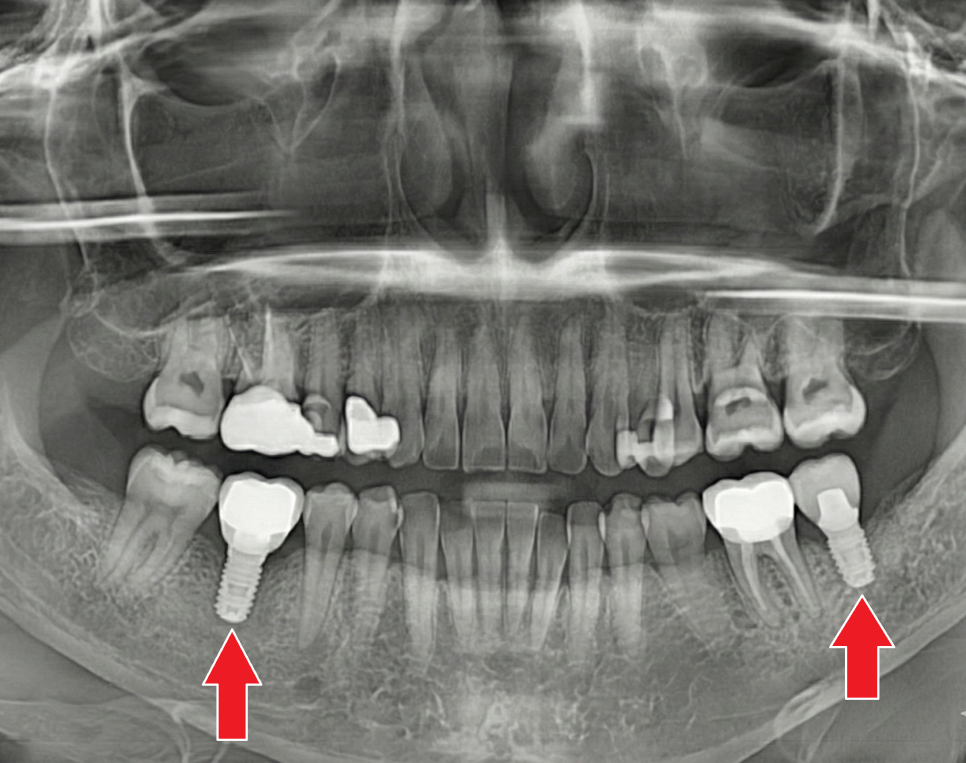

임플란트 완성

환자분은 4개월 정도 더 기다리며

임플란트와 뼈가 단단히 하나가

되기를 기다렸습니다.

짐작이 아닌 수치(데이터)로 유착 정도를

정확히 확인한 후 최종 보철물을 완성해 드렸습니다.

251030

이제는 양쪽 어금니로 마음 편히 식사하시는

환자분을 보며 저 역시 큰 보람을 느꼈습니다. ^^